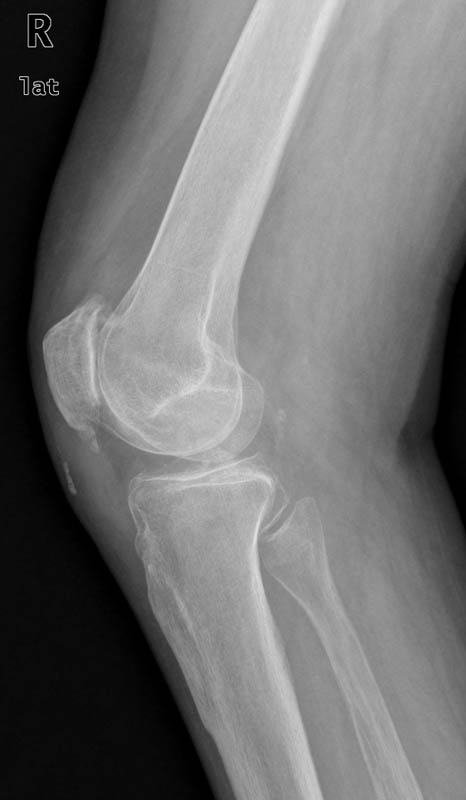

ACT artrosis muy severa de codo.